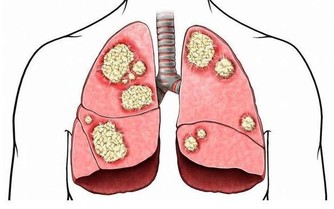

■懶事七:懶得刮鬍子,易患呼吸道癌症。

△健康影響:人體呼吸時排出的多種有害氣體都可滯留在鬍子上,再加上大氣中含有多種重金屬微粒被鬍鬚吸附,從而進入呼吸道。

研究發現,鬍子上存有多種有害物質,如苯、甲苯、氫硫化物、丙酮、氨等。

如果不能勤刮鬍子,這些有害物質就極易侵害呼吸道,加大患癌風險。